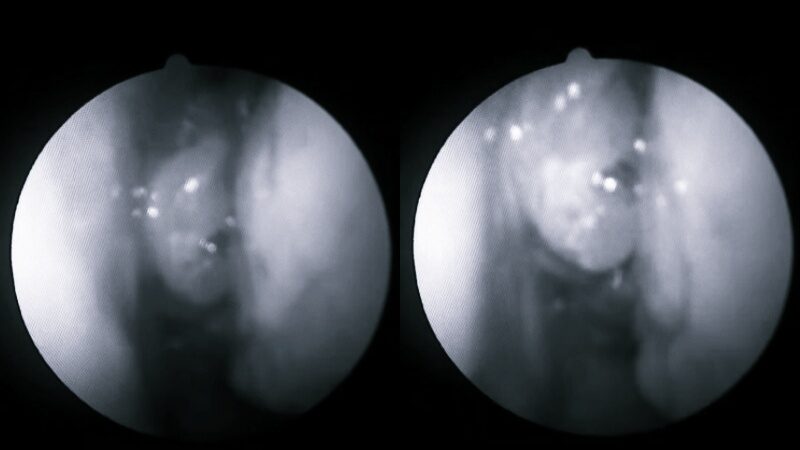

นพ.ติง เหมิงชาง กล่าวว่า เมื่อเขาใช้กล้องเอนโดสโคปเพื่อสำรวจโพรงจมูกด้านซ้ายของคนไข้ชายคนนั้นก็รู้สึกประหลาดใจที่เห็นก้อนเนื้อที่ชัดเจนมาก เมื่อดูจากสี จริง ๆ แล้วคาดว่าเป็นติ่งเนื้อจมูกธรรมดาในตอนแรก แต่เนื่องจากมีอาการเลือดออกอย่างเห็นได้ชัดจึงเป็นการยากที่จะเพิกเฉย

ดังนั้น แพทย์แนะนำให้ผู้ป่วยเข้ารับการตรวจชิ้นเนื้อเพื่อยืนยันว่าเป็นเนื้องอกเนื้อร้ายหรือไม่ จากนั้นผู้ป่วยได้รับการวินิจฉัยว่าเป็นเนื้องอก มะเร็งในโพรงจมูก และต่อมาผู้ป่วยก็ถูกส่งตัวไปที่ศูนย์การแพทย์เพื่อรับการรักษา